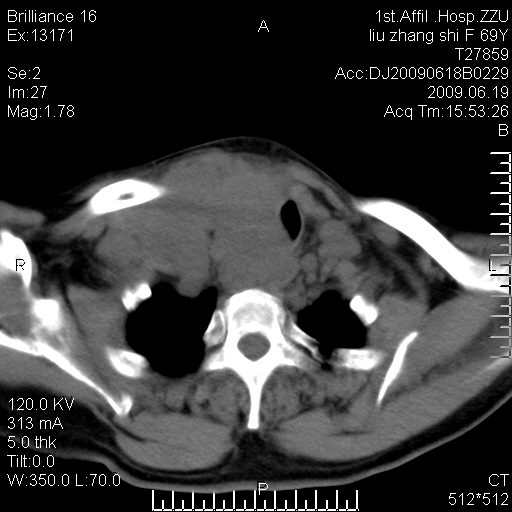

标题: CT26782:女,69岁,颈部占位,3天后公布病理结果。

【病理证实系列】女,69岁,颈部占位,有病理结果,3天后公布。(由于病例时间较久,临床资料不全,请网友见谅)本系列将有几百种常见、少见及罕见病例,均经病理证实。病例资料来自郑州大学第一附属医院。与网友共享,本人有空就发。

支持甲状腺癌广泛侵及周围结构并颈部淋巴结转移。

鉴别:淋巴瘤、恶性神经源性病变、恶性纤维组织细胞瘤。

病理结果:颈部非霍奇金淋巴瘤。

右侧甲状腺确实有问题